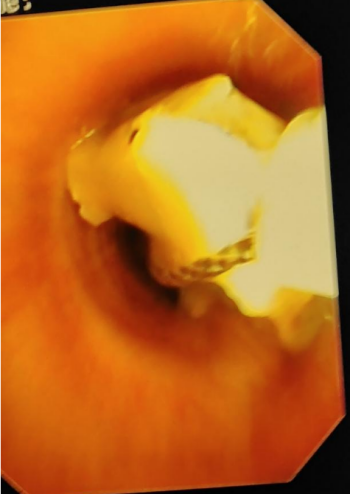

纤支镜检查中所见的取异物过程中异物被圈套套住

胸部CT检查发现异物在左侧支气管为确保患者安全,医生们决定立刻为刘建军实施纤支镜下异物取出术。呼吸内镜诊疗中心副主任医师刘超群从家中赶来,迅速为刘建军进行了纤支镜检查及支气管异物取出术。术中,医生成功从患者支气管内取出两块正方形的甲鱼背壳骨片。从患者入院到异物取出,整个过程仅用时1小时,确保了患者的安全。